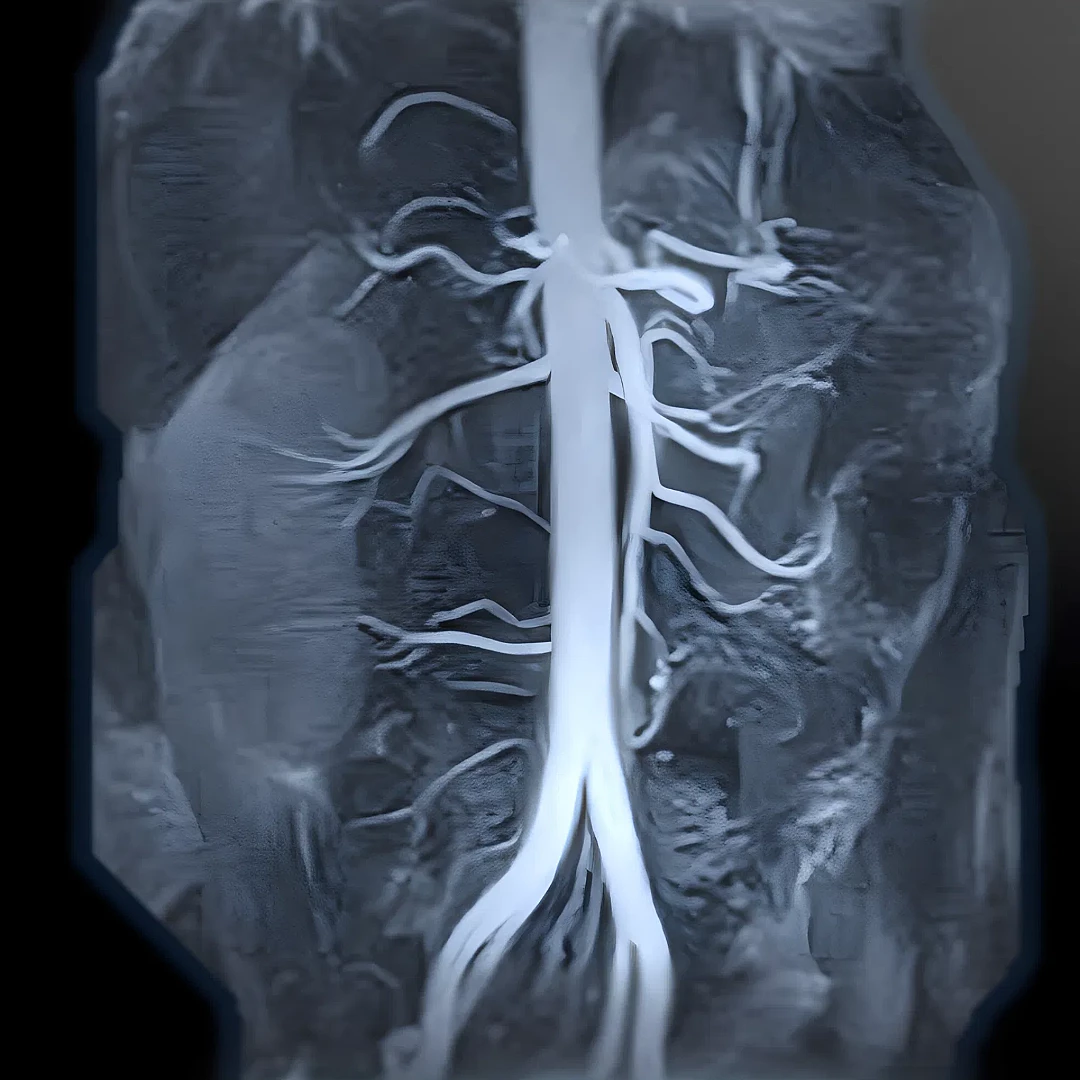

Aortic & Peripheral MR Angiography

Aortic and Peripheral MR Angiography visualizes blood flow in the aorta and peripheral arteries to detect blockages, aneurysms, or vascular disease. This non-invasive, radiation-free scan offers detailed vascular mapping for accurate diagnosis and treatment planning.